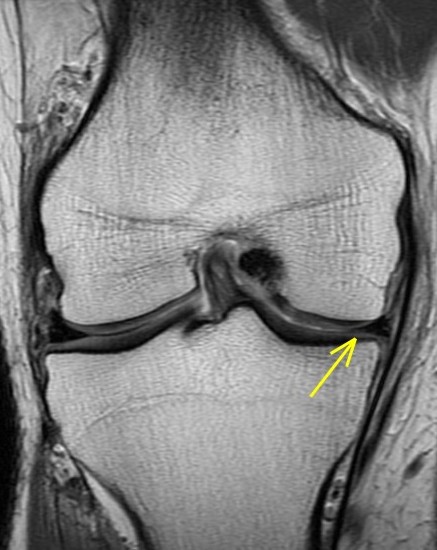

44 y/o male recreational runner. 2 week history of medial pain. r/o mmt.

Bone marrow edema is the radiologists friend. The posterior horn tear is easy to see. The displaced meniscus flap into the coronary recess adjacent to the body of the meniscus isnt so easy to see. The presence of bone marrow edema should alert us to the possibility of adjacent pathology leading to the reactive changes in the bone.

Unstable displaced medial meniscus tear( RID2772 ) with reactive tibial edema